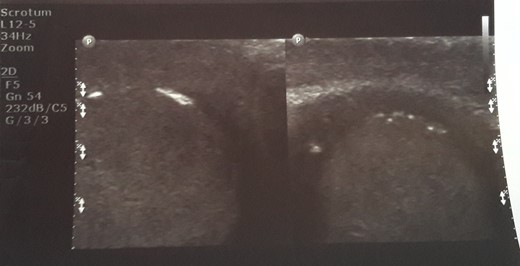

Initial sonographic findings were suggestive of epididymo-orchitis. The testis was well perfused and in normal position (Fig. 1). He was admitted for 3 days to start intravenous anti-inflammatory and antibiotic treatment and discharged under antibiotic treatment. Re-examinations were scheduled to assess treatment. On first reexamination, a week later, edema had subsided and the testis appeared hard, indurated and painless (Fig. 2). Ultrasound was still suggestive of epididymo-orchitis. Nevertheless suspicion for a testicular tumor was raised because of persistence of clinical and sonographic findings. An earlier appointment was scheduled this time. Five days later, at the second reexamination, another ultrasound showed reduced testicular perfusion that reached only the periphery of the testicular parenchyma (Fig. 3). The boy was operated as an emergency. Intraoperatively testis was non-twisted, with normal vas and vessels that ended in a necrotic testicular parenchyma. The testis was dark brown, hard on palpation and no blood came out when incised (Fig. 4). Right orchidectomy was performed. Since the exact cause of testicular necrosis was still unkown at the time of operation a left orchidopexy was performed to protect the only surviving testis from any future risk of torsion. The boy was discharged the next day. Histology showed a case of epididymitis nodosa and ruptured sperm granuloma that caused vascular compression, thrombosis and testicular necrosis (Fig. 5). More specifically, it showed proliferation of small ducts and gland-like structures in the walls of the vas deferens and epididymis in response to fluid and sperm dissection into the interstitium secondary to mechanical obstruction and increased intraluminal pressure. These findings are extremely rare in pediatric patients. The boy had an uneventful postoperative course and was discharged 2 days after surgery able to travel by sea to his home island.

Initial sonographic findings were suggestive of orheoepididymitis.